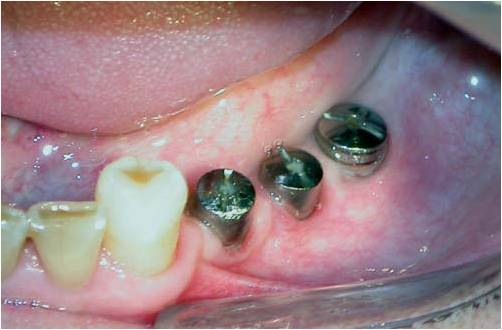

Figs. 8, 9 e 10 - Os implantes já perfeitamente fixados, com a suave deposição do plexo alveolar inferior na sua loja cirúrgica.

Uma vez localizado o canal mandibular sua parede é cuidadosamente retirada, liberando-se progressivamente o feixe neurovascular. Eventualmente, por uma outra técnica há necessidade de se realizar a transposição do nervo incisivo para se obter um afastamento satisfatório do NAI. Após o afastamento do feixe, realiza-se a fixação dos implantes, seguindo o protocolo correspondente, utilizando-se da cortical basal ou não, para obter uma melhor estabilidade inicial (24, 30) (Figs. 8, 9 e 10). Na seqüência o NAI é acomodado passivamente na loja óssea quando apenas lateralizado (12, 29).